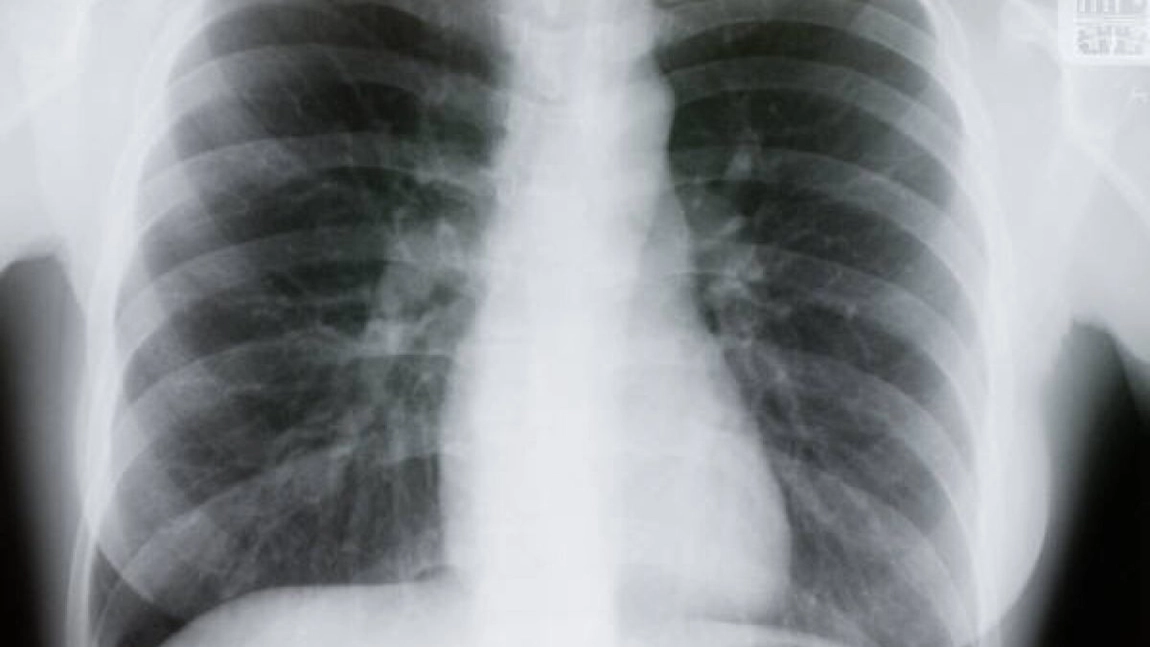

Radiografia pulmonară, adică cea toracică, poate identifica prezența calciului în inimă sau în vasele de sânge. Prezența acestui element poate semnala grăsimi sau alte substanțe ori leziuni ale valvelor inimii, arterelor coronare sau sacului care îmbracă inima.

În urma unei radiografii la plămâni, pot fi descoperite fracturi ale coastelor sau ale coloanei vertebrale, ori alte probleme ale oaselor.

Totodată, cu ajutorul radiografiei pulmonare, poate fi supravegheată recuperarea unei intervenții chirurgicale la nivelul pieptului (inimă, plămâni sau esofag).

Nu în ultimul rând, radiografia pulmonară este indicată și pentru vizualizarea și monitorizarea unui stimulator cardiac, a unui defibrilator sau un cateter. În acest caz, radiografia este utilizată după plasarea unor astfel de dispozitive, pentru ca medicul să se asigure că sunt poziționate în locul potrivit.

După vârsta de 40 de ani, radiografia la plămâni este de o importanță majoră. Acest procedeu neinvaziv ajută la prevenirea cancerului pulmonar, afecțiune care este pe primul loc în rândul bărbaților, în special la cei care fumează.